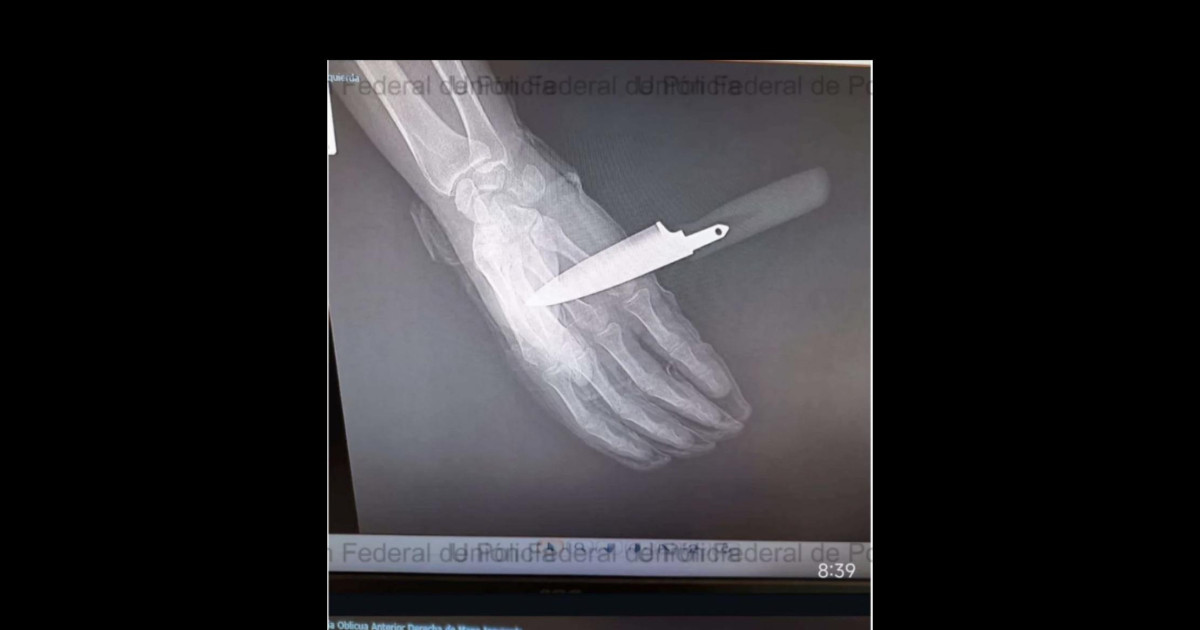

Te intentan apuñalar en el pecho varias veces, el chaleco para el cuchillo, la última puñalada te atraviesa la mano... pues lo normal sería irte al hospital corriendo. Pues no.... Tienes que irte a comisaría, con el cuchillo clavado en la mano, a llevar al detenido y que lo metan en los calabozos.